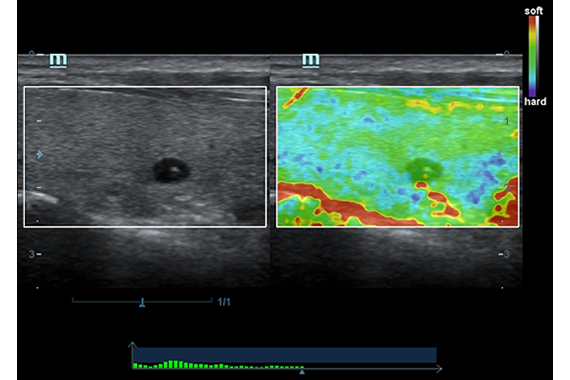

Эластография:

Компрессионная, Сдвиговая

Эластография сдвиговой волной/Эластометрия:

Да

Компрессионная эластография:

• Natural Touch Elastography - опция оценки эластичности ткани (эластография), с программой анализа. Действует на линейных датчиках 7L4A, L14-6NE и L9-3E